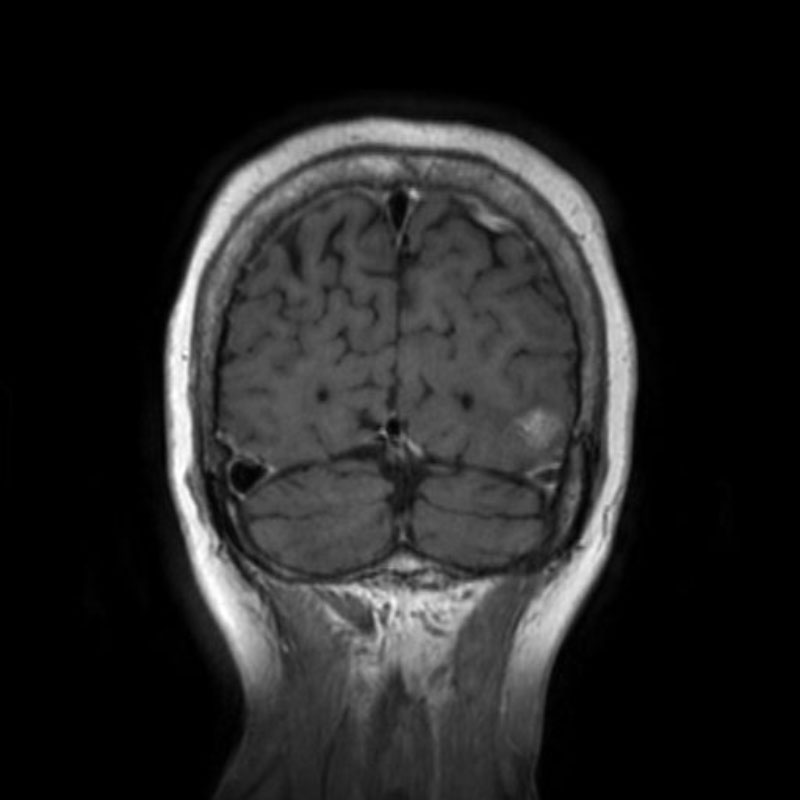

断層撮影

手術前1

手術前2